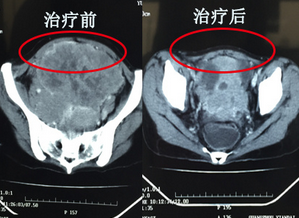

目前,玉麗雅已經(jīng)接受了5次介入治療,2次冷凍治療,在這過程中,腫瘤從原來的14cm已經(jīng)縮小到8cm。玉麗雅的主治醫(yī)院龐醫(yī)生告訴我們,她的治療效果很明顯,繼續(xù)接受治療,腫瘤能進一步縮小,讓我們來期待又一個抗癌奇跡吧。